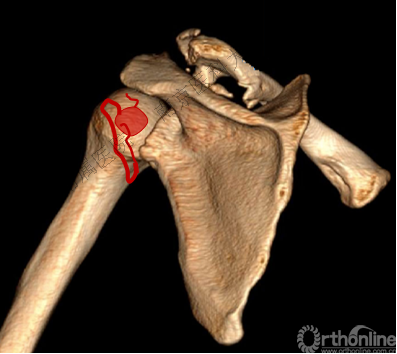

四、分型

肩关节后脱位:

Ⅰ型: +肱骨颈骨折。

Ⅱ型: +肱骨颈骨折+小结节骨折(病例3)。

Ⅲ型: +肱骨颈骨折+小结节骨折+大结节骨折(病例2),以骨折线向肱骨近端外侧壁延伸为另一特征。

五、反Hill-Sachs 损伤对肩关节稳定性的影响

1.反Hill-Sachs损伤范围对肩关节后方稳定性具有决定性的影响。

2.常规的影像学测量方法不能准确反映损伤范围。

1.肩胛盂后侧可以因骨折导致缺损(反Bankart损伤),或发生盂肱韧带附着处的撕脱骨折。

3.反Hill-Sachs损伤合并反Bankart损伤被Moroder命名为“双极损伤”。

4.δ角是发生肱骨头后脱位所需的肩关节内旋角度,在双极损伤中δ角减小,所以在双极损伤中,即使较轻的反Hill-Sachs损伤也需要修复。